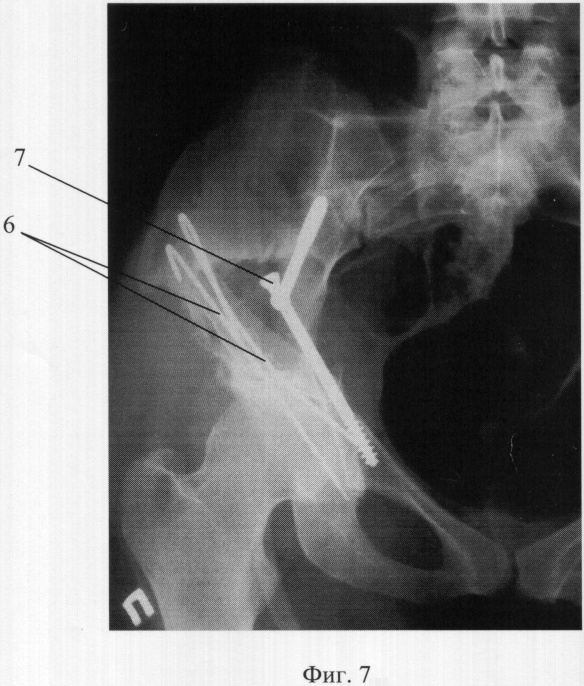

Фиг.7. Рентгенограмма восстановленного сустава. 6 – фиксирующие спицы, 7 – спонгиозные шурупы.

После тщательной криогенной и У3-обработки зоны поражения в сохранившуюся полость вертлужной впадины, с напуском на отсутствующий участок, уложены никелид-титановая сетка и, поверх нее, пластина из пористого никелида титана.

Отсутствующий костный участок сформирован аутокостью из гребня подвздошной кости путем перемещения костного лоскута и плотной укладки на вышеупомянутый имплантат в области его напуска над дефектом. Получившийся слоистый композит фиксирован к тазовой кости спицами 6 (фиг.7). Патологическая подвижность внутреннего тазового кольца блокирована введением спонгиозных шурупов 7 в лонный и подвздошный участки и заполнением дефекта, вкупе с головками шурупов, медицинским цементом. Бедренная кость головкой водворена в восстановленную вертлужную впадину.